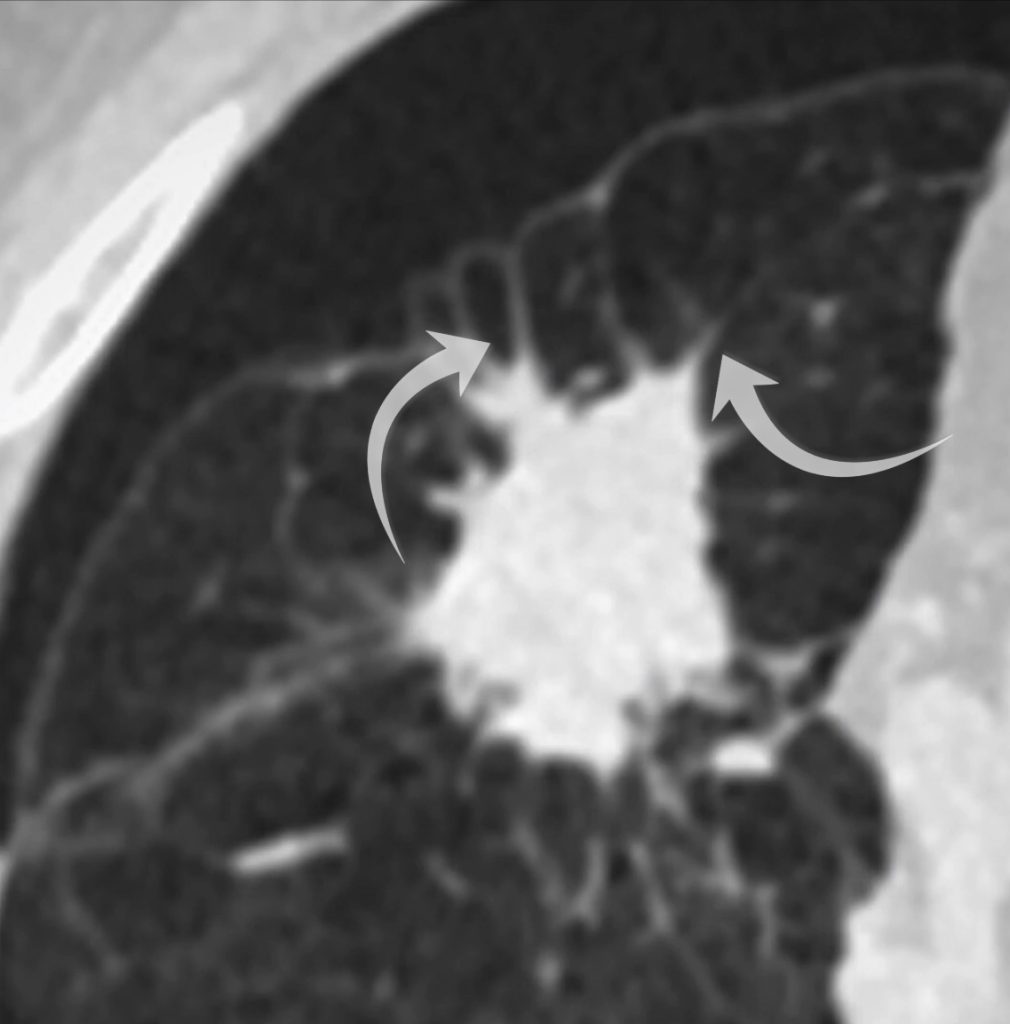

The chest drain is out side of the pleura (bottom arrow) and the pneumothorax persists (top arrow). There is a small right pleural effusion.

Examining the right upper lobe lesion in more detail, we see small spicules radiating from it. A spiculated lesion raises concern for a primary lung cancer. In my experience however you need to adopt a little caution when the underlying lung is abnormal as with severe emphysema a lot of lesions can look spiculated!

The right upper lobe lesion is spiculated.